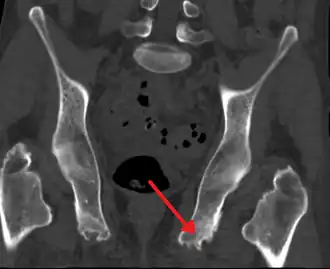

Une enthésiopathie ou enthésopathie est une inflammation d'une enthèse. Les enthèses sont les zones où s'insèrent sur les os les capsules articulaires, tendons et ligaments.